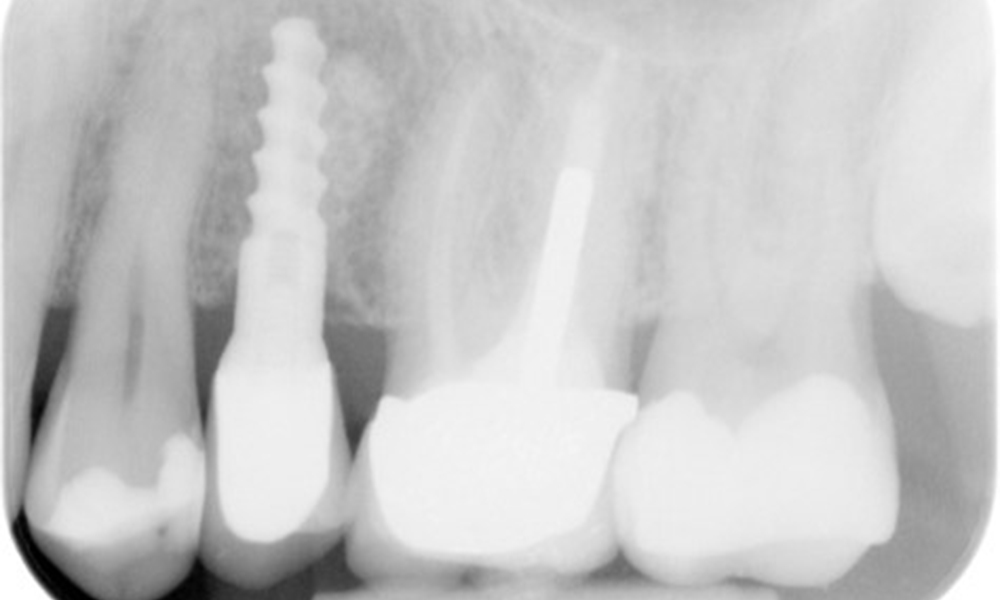

OPG: 29.02.2024

Zahnfilme (bzw. Bissflügelröntgen)

Zahnfilme (bzw. Bissflügelröntgen) aufgenommen am: 18.02.2021